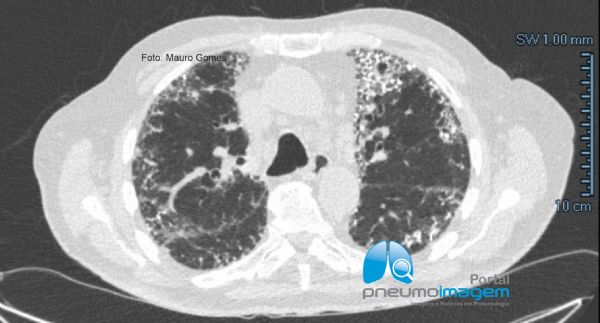

Nesses cortes podem-se observar alterações intersticiais com fibrose caracterizadas por reticulado e bronquiectasias de tração com predomínio periférico e basal. As lesões se estendem desde as regiões apicais (menor intensidade) até as bases (maior intensidade). O padrão é de provável pneumonia intersticial usual (PIU). Observe que se associam às lesões múltiplos focos dendriformes de calcificação, compatível com ossificação pulmonar.

In these sections, interstitial changes with fibrosis characterized by reticulate and traction bronchiectasis with peripheral and basal predominance can be observed. The lesions extend from the apical regions (lower intensity) to the lower lobes (higher intensity). The characteristic pattern is probable usual interstitial pneumonia (PIU). Multiple dendriform foci of calcification are associated with lesions, compatible with pulmonary ossification.